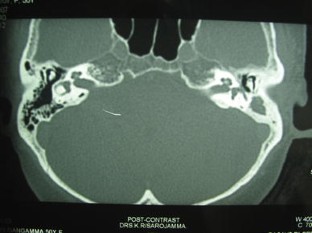

Fig. 2